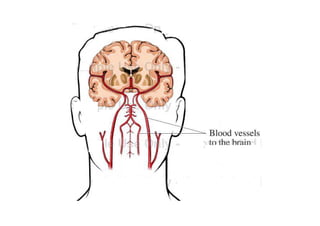

Relações anatômicas e Circulação Arterial

figura

• A artéria vertebral é muitas vezes o primeiro e o maior ramo da artéria

subclávia.

Ela sobre para entrar no forame do processo transverso da 6ª vértebra

cervical. Continua a subir, encerrada nos anéis ósseos formados pelos

forames transversos.

Depois de emergir do forame transverso do atlas, a artéria vertebral

prossegue para curvar-se posterior e medialmente em torno da massa

lateral do atlas.

A artéria vertebral a seguir passa através do forame magno e na borda

inferior da ponte, une-se com a artéria vertebral do lado oposto para

formar o tronco basilar.

As artérias cerebelares póstero-inferiores (ACPIs) saem das artérias

vertebrais imediatamente antes delas se juntarem uma à outra